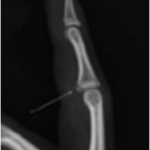

Suggest X-ray

Fig 1: Basic Treatment

A metal splint being used to treat a finger dislocation. It does not allow a full range of motion.